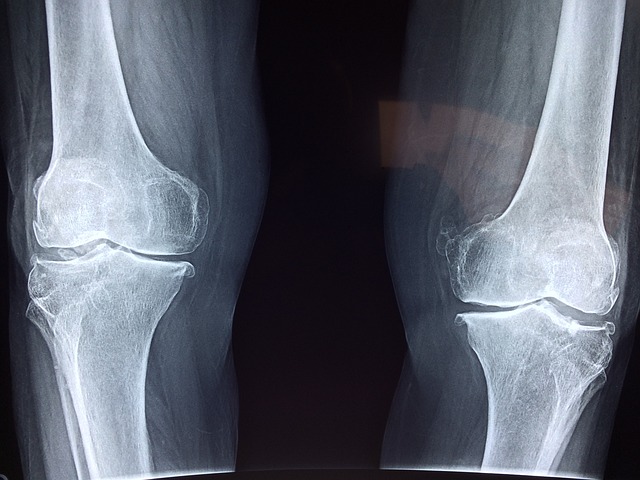

4. 통풍의 진단

통풍을 진단하기 위해서는 몇 가지 검사를 시행합니다:

- 혈액 검사: 혈중 요산 수치를 측정하여 고요산혈증 여부를 확인합니다.

- 소변 검사: 소변을 통해 요산 배출량을 확인합니다.

- 관절액 검사: 관절에서 체액을 채취하여 요산 결정 유무를 확인합니다.

정기적인 검사를 통해 요산 수치를 모니터링하는 것이 중요합니다. 통풍 증상이 없더라도 고요산혈증이 있는 경우 통풍 발작의 위험이 높아지기 때문입니다.